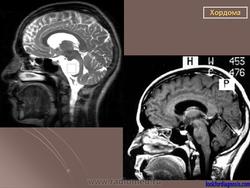

Крестцово-копчиковая хордома.